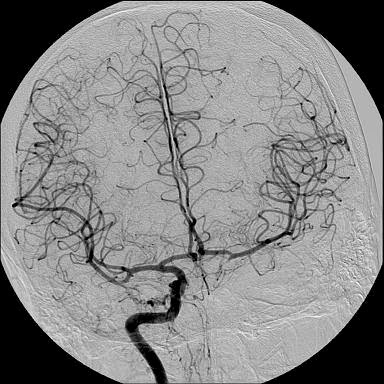

Primeiramente, o procedimento de angiografia nada mais é que uma técnica de visualização dos vasos sanguíneos.

Angiografia (também conhecida como arteriografia) é uma técnica de imaginologia médica utilizada para visualizar o interior dos vasos sanguíneos, em particular as artérias.

O procedimento é realizado por um radiologista intervencionista, que vai injetar um agente de contraste radiopaco em seu vaso sanguíneo. Esta é uma substância que fará com que os vasos sanguíneos apareçam mais claramente durante o exame. O radiologista intervencionista utilizará a fluoroscopia para a orientação e a aquisição das imagens.

Uma arteriografia diagnóstica é um procedimento que envolve a inserção de uma agulha ou cateter no interior de uma artéria, utilizando injeção de um agente de contraste e, em seguida, observa-se o vaso por meio do equipamento de imagem.

Uma das utilizações mais comuns dos angiogramas é identificar bloqueios ou estreitamento de vasos sanguíneos que podem interferir no fluxo sanguíneo normal em muitas partes do corpo, incluindo o cérebro, coração, abdômen e pernas. Em muitos casos, o radiologista intervencionista pode tratar um vaso sanguíneo bloqueado enquanto o angiograma é realizado sem necessidade de cirurgia.

Em relação à angiografia cerebral, dispôs o site da Sociedade Brasileira de Neurorradiologia Diagnóstica e Terapêutica (SBNR):

A Angiografia cerebral consiste em um exame neurorradiológico realizado após punção femoral e que com auxílio de cateteres de diferentes formatos e de um fia guia com o objetivo de avaliar a circulação intracraniana com a visualização dos vasos assegurados em decorrência de uso de contraste não iônico e de radiação ionizante (raios X).